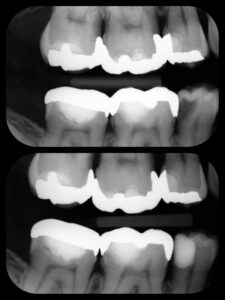

虫歯が深くても、神経を残せる可能性があります!

当院では、歯の寿命を左右する「神経」を可能な限り保存する治療に取り組んでいます。

✅ 再発リスクを抑える精密治療

「神経を抜くしかない」と言われた場合でも、保存できるケースがあります。大切な歯を守るためのベストな選択肢を一緒に考えましょう。

ダイレクトボンディング(自費のプラスチック治療)は一歯¥33,000〜55,000です。

範囲によって変わるので一度ご相談ください。